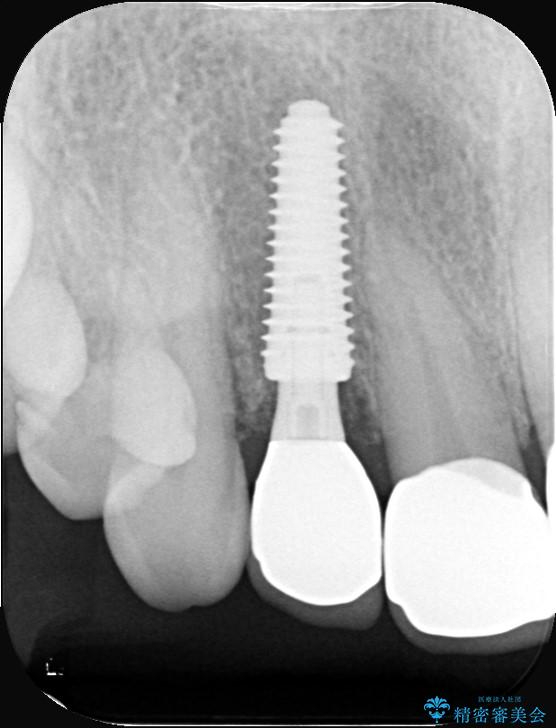

インプラント治療は、低侵襲で短期間に行える「抜歯即時インプラント治療」を選択しました。

この方法は、抜歯したその日にインプラントを埋入し、手術が1回で済むのが大きな特徴です。

治療期間も短く、抜歯からわずか3か月でオールセラミッククラウンを装着することができます。

また、オペ当日には仮歯まで装着するため、見た目を気にせず普段通りの生活を送ることができます。